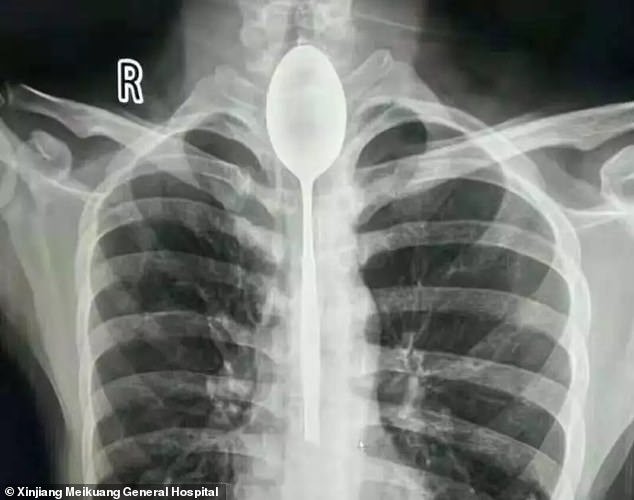

Depois de um jantar de amigos e uns copos a mais, começaram as irresponsabilidades. Tudo aconteceu na China, quando um homem engoliu uma colher de 20 cm depois de perder uma aposta. Porém, como não teve problemas respiratórios, bebia e comia normalmente, deixou-se ficar. Viveu assim durante um ano. O alarme suou quando esse homem chinês levou um soco no peito e a colher perfurou-lhe o esófago. Começou a ter dores fortes e dificuldades em respirar, o que o levou a ir ao hospital Xinjiang Meikuang. “Fiquei chocado. Nunca tinha visto algo assim. Quando internamos o paciente, o seu esófago …